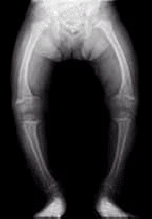

El raquitismo es una enfermedad infantil que se produce cuando existe una deficiencia en la mineralización de los huesos del niño, cuando estos se encuentran en la fase de crecimiento. La patología se caracteriza por la ausencia de vitamina D, tan esencial para mantener los niveles adecuados de calcio y fósforo en el organismo, se trata del raquitismo carencial.

Ahora, un grupo de investigadores alemanes, norteamericanos y españoles (de Zaragoza), acaban de descubrir una nueva forma de raquitismo hereditario. El peso de la investigación ha recaído en el Instituto de Genética Humana de Munich (Alemania) y el descubrimiento ha sido realizado en 9 miembros de tres familias de distintas nacionalidades que presentaban la nueva forma de raquitismo hereditario.

Hasta ahora, los casos de raquitismo conocidos de origen hereditario, son producidos por la mutación de un gen (FGF23). La nueva variante se encuentra ligada al gen DMP1, los padres son portadores de la enfermedad pero no la padecen y el niño manifiesta la enfermedad más tarde que si padeciera raquitismo carencial (a partir de los seis meses de edad). Un factor importante para padecer esta enfermedad sería la escasa exposición a la luz solar.